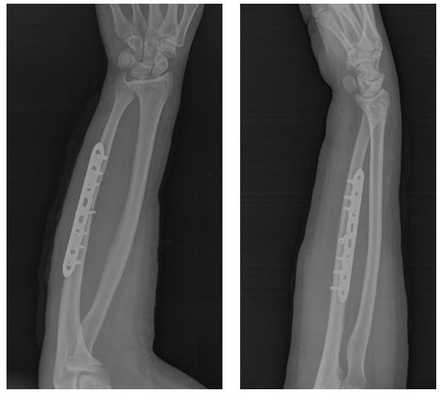

Клинический пример хирургического лечения перелома локтевой кости.

Пациент П. 39 лет, получил перелом локтевой кости в результате прямой травмы (падение на бордюрный камень с упором на согнутую в локтевом суставе руку).

Обратился в РТП, была наложена гипсовая повязка, лечился консервативно.

Обратился на консультацию в К+31. С целью ранней реабилитации, активизации, профилактики замедленной консолидации и формирования ложного сустава, полного восстанволения функции конечности предложено оперативное лечение - открытая репозиция, остеосинтез перелома пластиной и винтами Synthes.

Пациент госпитализирован с приёма, проведено полное предоперационное обследование, операция выполнена в день обращения.

В случае простых переломов, где линия перелома образована 2 основными крупными фрагментами (возможно наличие небольшого количества мелких фрагментов не препятсвующих стабильной фиксации) выполняется остеосинтез при помощи пластины и винтов с достижением максимальной механической стабильности в зоне перелома и компрессии между собой отломков.

Такой остеосинтез был впервые предложен и претерпел дальнейшее широкое распространение благодаря международному сообществу травматологов - ортопедов AO\ASIF.

После выполнения стандартного доступа к локтевой кости, мобилизации костных отломков, осуществлена их репозиция при помощи костодержателей.

На рентгенограммах после операции остеосинтез выглядит так.

Такой остеосинтез крайне надёжен и позволяет давать полную амплитуду движений непосредственно сразу после операции. С целью заживления послеоперационной раны и минимизации боли в раннем послеоперационном периоде (первые 2 недели после операци) рекомендуется ношение косыночной повязки и использование грелки со льдом местно по 20-30 минут до 5 раз в день.

После снятия швов можно использовать руку для бытовых нужд. Через 6 недель выполняется рентгенконтроль, при наличии признаков сращения нагрузка увеличивается до полной. Однако форсированные физические нагрузки противопоказаны до 3 месяцев после операции.